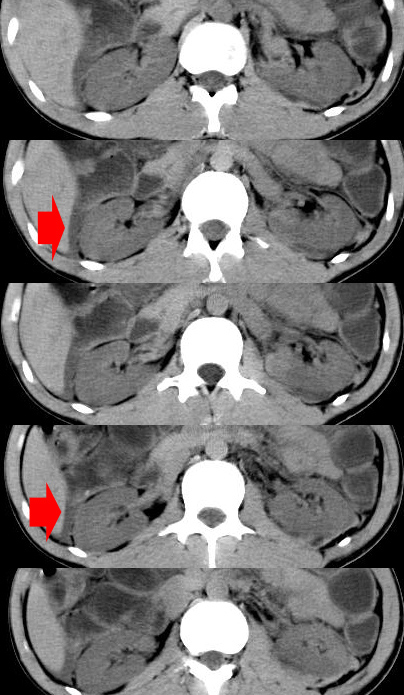

m-25y 高空堕落 12 月5号

12月7号病人尿量200ml/24h 急查双肾ct

左肾挫裂伤并肾周血肿;

左肾挫裂伤并肾周血肿

支持:1、左肾挫裂伤并肾周血肿;

2、少量腹水;

3、左肾旋转不良;

4、反射性肠淤张。